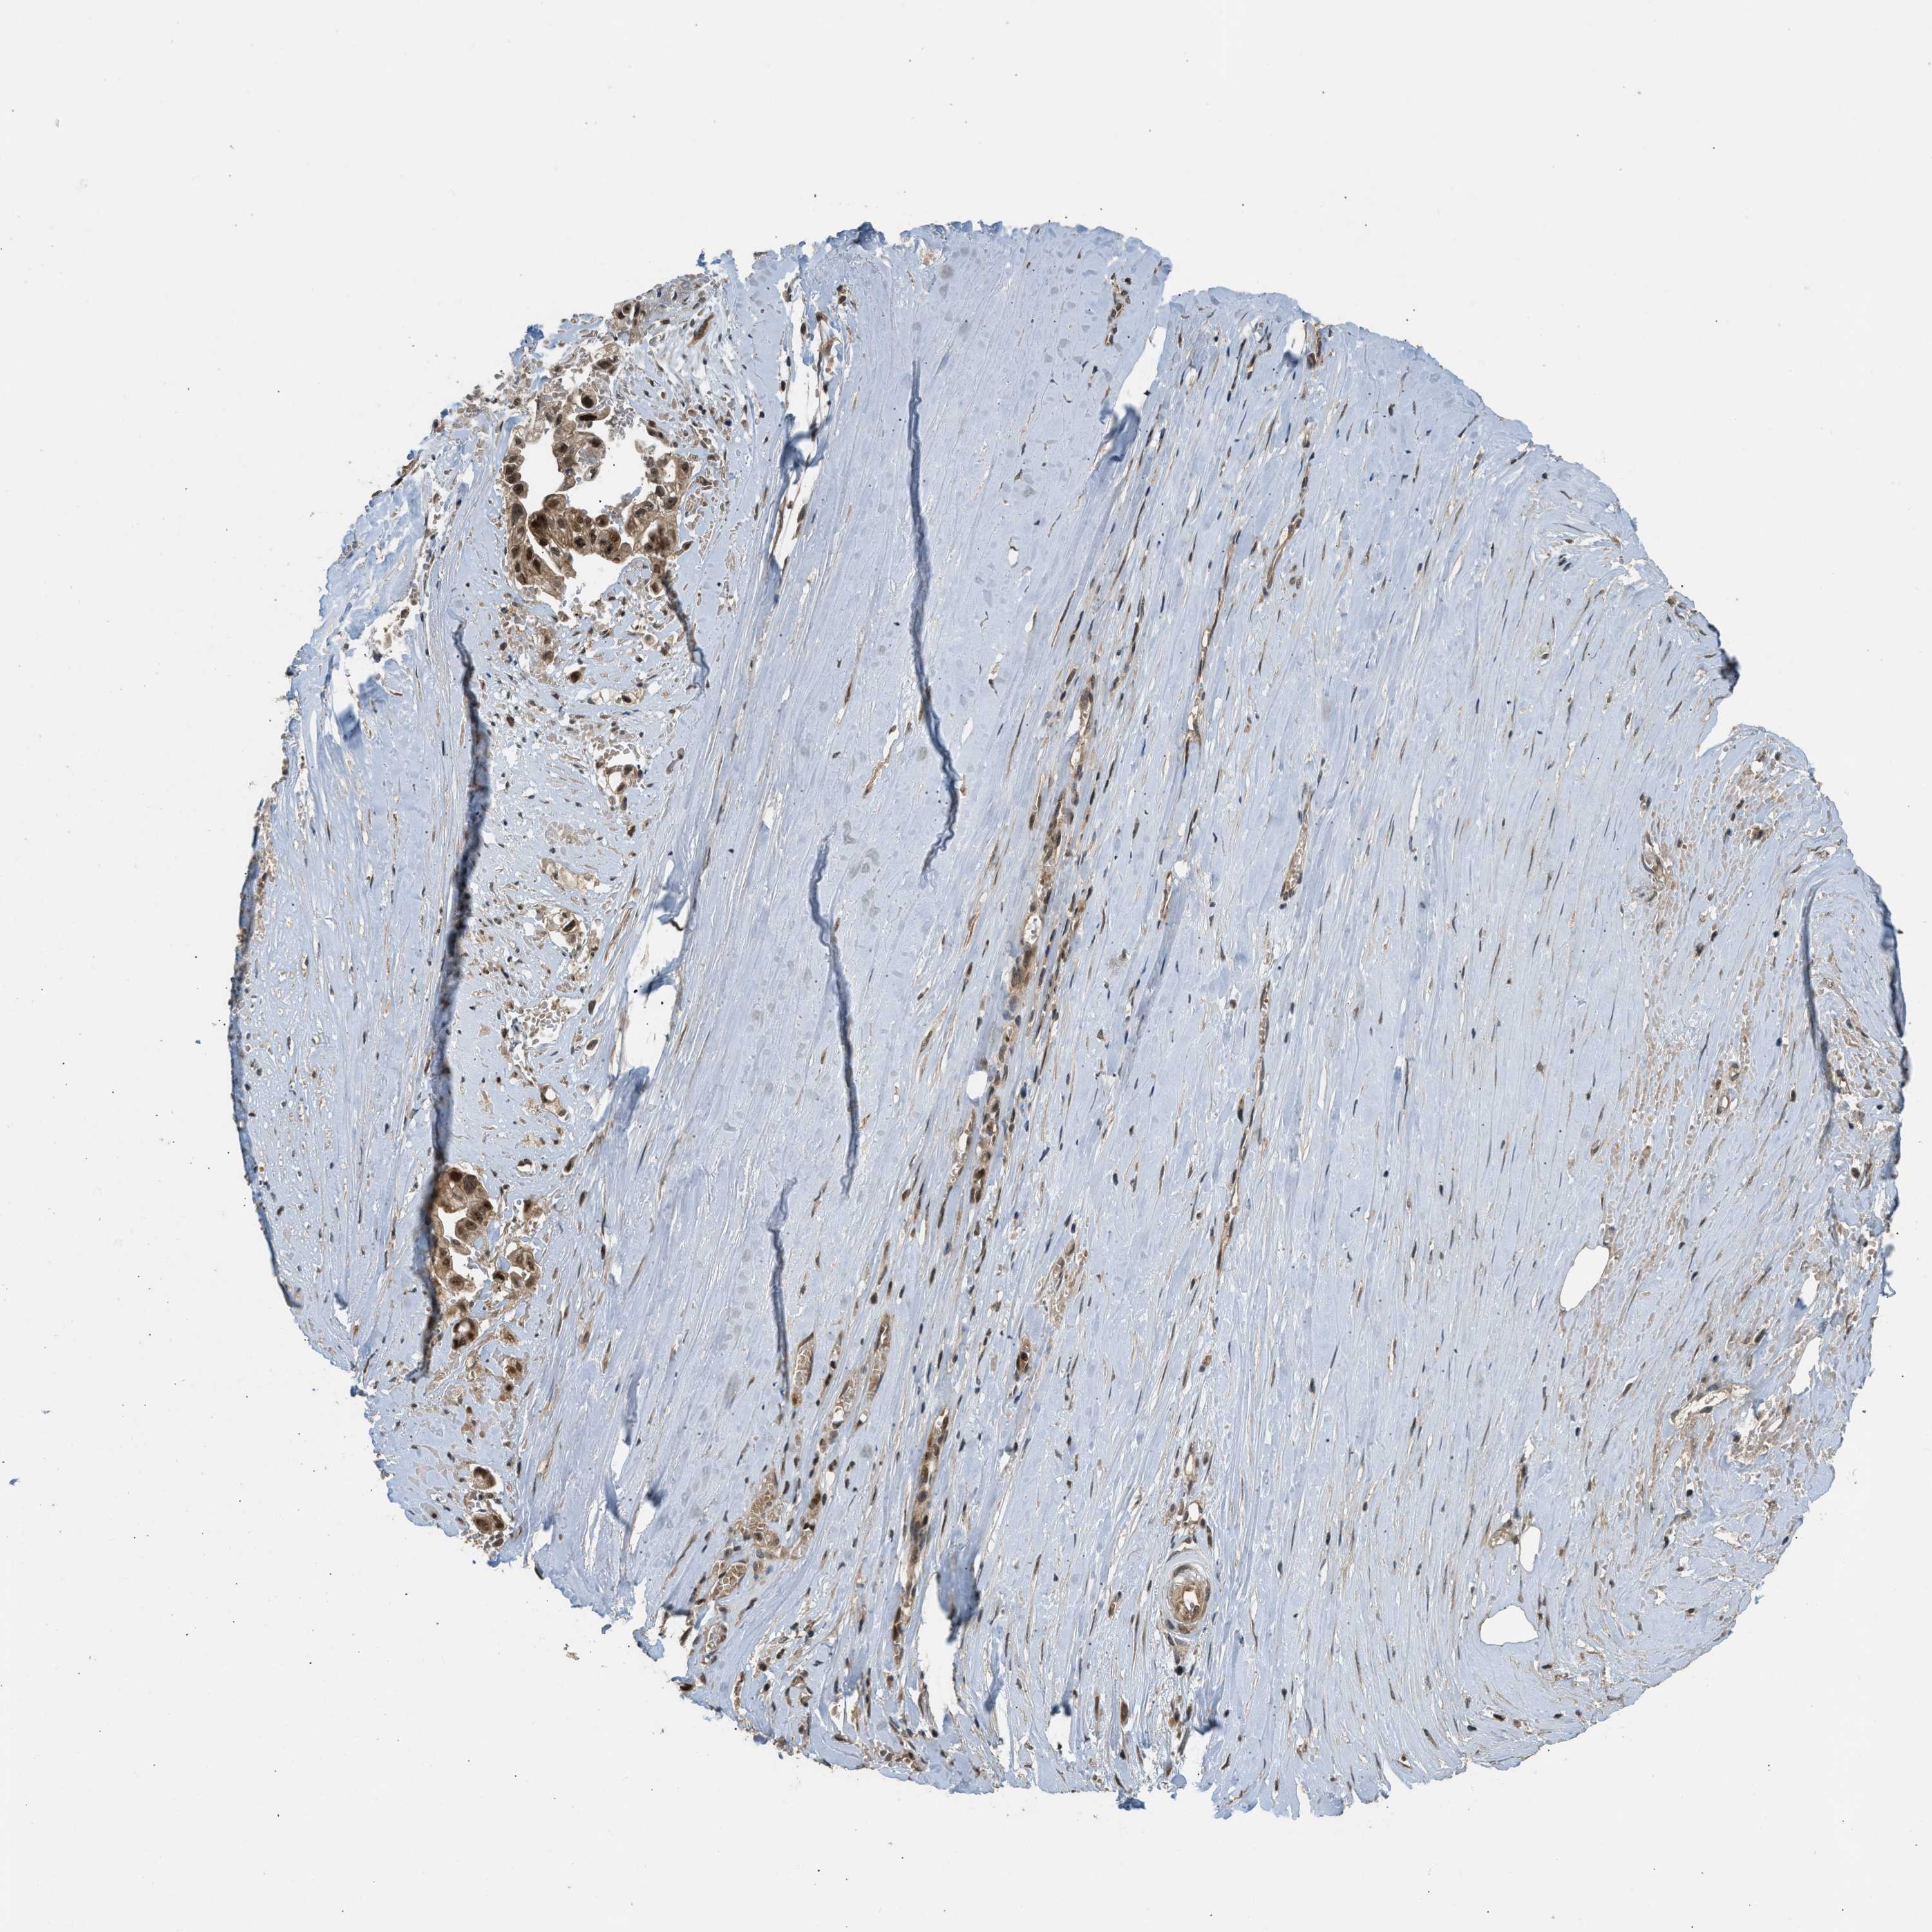

LIVER CANCER - Protein expressioni

A mouse-over function shows sample information and annotation data. Click on an image to view it in a full screen mode. Samples can be filtered based on level of antibody staining by selecting one or several of the following categories: high, medium, low and not detected. The assay and annotation is described here.

Note that samples used for immunohistochemistry by the Human Protein Atlas do not correspond to samples in the TCGA dataset.

Antibody stainingi

Antibody staining in the annotated cell types in the current human tissue is reported as not detected, low, medium, or high, based on conventional immunohistochemistry profiling in selected tissues. This score is based on the combination of the staining intensity and fraction of stained cells.

Each image is clickable and will lead to virtual microscopy that enables deeper exploration of all samples and also displays staining intensity scores, fraction scores and subcellular localization as well as patient and tissue information for each sample.

Antibody HPA018527

Staining

High

Medium

Low

Not detected

Intensity

Strong

Moderate

Weak

Negative

Quantity

>75%

75%-25%

<25%

None

Location

Nuclear

Cytoplasmic/membranous

Cytoplasmic/membranous,nuclear

Cholangiocarcinoma

Carcinoma, Hepatocellular, NOS